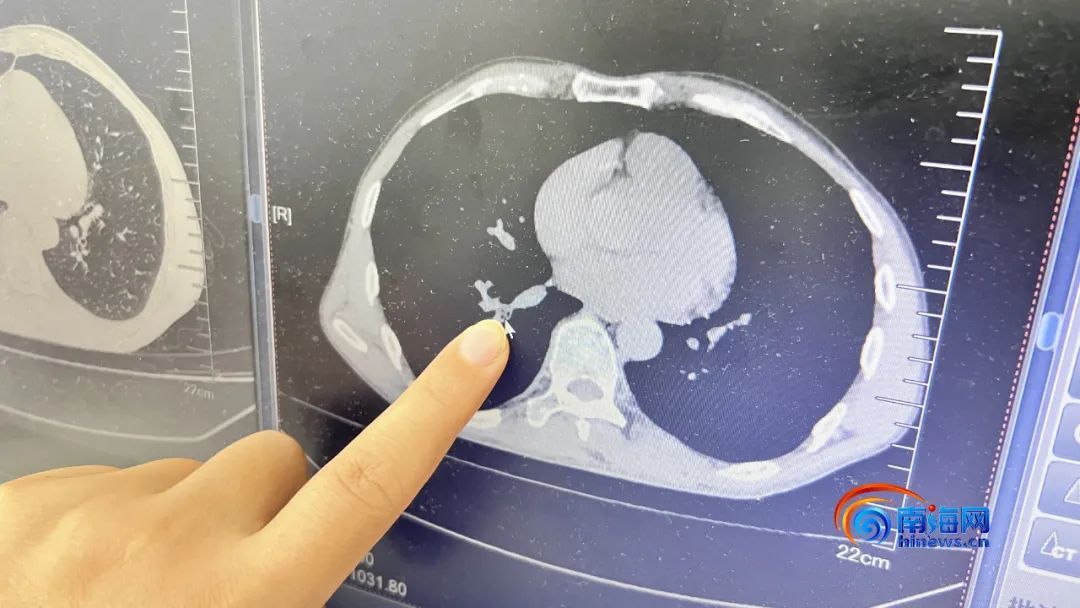

对此,林玲医生为患者做胸部CT检查,发现患者右下叶外后基底段有一块阴影,结合其病史,考虑是有异物。

蟑螂呛入了支气管中。记者 王洪旭 摄